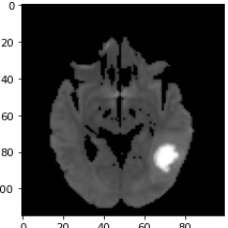

As a first example, we consider a neuroradiological application, where we aim for dividing MRI images showing an abscess into the regions healthy, abscess and edema. The left column in Fig. 6 shows three channels of an MRI dataset using diffusion weighted imaging (DWI), apparent diffusion coefficient (ADC), and T2 sequence. As preprocessing, the ADC maps and T2 images were windowed and standardized to have intensity values between . The second column shows the segmentations obtained by MMCV. Here we chose a weighted linear combination of the three images as the input image. This strategy was found to provide better results than treating the three images as separate channels. We selected the regularization parameter empirically so that it led to the best results. The remaining columns of Fig. 6 show the segmentation masks corresponding to four different regularization parameters. Smaller values of result in quite inaccurate results containing many false positives. The results in the last row, which were obtained by setting the regularization parameter to , show an improvement compared to the ones in the previous columns. Quantitative evaluation metrics are summarized in Table 3.

For the second medical example, we use image from the brain tumor segmentation (BRATS) challenge 2015 dataset; see https://www.smir.ch/BRATS/Start2015. The channels in this case consist of contrast-enhanced T1-weighted (T1c), T2 and fluid attenuated inversion recovery (FLAIR) images. Channels contain complementary information allowing accurate diagnosis and quantification of tumor growth. The top row in Fig. 7 shows the input images highlighting a different region of the tumor. Again, we exploit the information contained in different sequences by employing them as separate input channels. The proposed method is thus able to use this complementary information to delineate the different tissues and demonstrates solid results for this concrete example from medicine. The fact that the proposed energy functional can be applied directly to the given images, makes it particularly suitable for medical image segmentation.